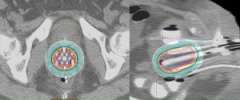

An alternative to this is to use CT compatible applicators and to use CT imaging. The advantage of this is that CT imaging allows you to see the anatomy in more detail than on X-rays. For example, a CT image with a vaginal applicator in place looks like the following:

CT Scan

One can actually "see" the anatomy including the bladder (yellow) and rectum (brown). The cylinder is outlined in red. By being able to clearly see things we can more effectively optimize the radiation dose to the target and limit the dose to normal tissues.